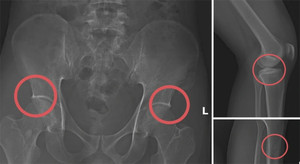

Chịu đục xương để trục lợi bảo hiểm, với chính cơ thể mình mà còn đối xử tàn nhẫn như vậy thì họ sẽ đối xử ra sao với người khác khi có cơ hội kiếm lợi?